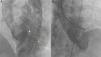

Right axillary artery access was obtained under local anesthesia as the delivery catheter length precluded a femoral artery approach. The LV angiogram with a 6F pigtail (Cordis Corporation, Miami, FL, USA) in left anterior oblique view with cranial angulation showed a large pseudoaneurysm arising from the basal inferolateral LV wall measuring 69 mm×92 mm with a connecting neck measuring 14 mm (Figure 2). A 0.035″ angled-tip hydrophilic glidewire (Terumo Interventional Systems, Japan) was placed in the aneurysm cavity through the communicating orifice using a 6F Judkins Right diagnostic catheter (Cordis Corporation, Miami, FL, USA), then a 0.038″ J-tipped Amplatz Super Stiff exchange wire (Boston Scientific, Marlborough, MA, USA) was substituted for the glidewire with the help of the catheter. A 9F delivery system (Cook Medical, Bloomington, IN, USA) was advanced over the Super Stiff wire and the distal tip was advanced into the pseudoaneurysm cavity. A 20 mm Amplatzer septal occluder, oversized by 6 mm, was deployed across the defect. Post-procedure LV angiography through the same sheath confirmed stable device position with minimal contrast leak foaming through the device. The post-procedure course was uneventful, with improvement in symptoms of heart failure from class III to class II and significantly increased exercise capacity. Follow-up echocardiography after a month showed complete closure of communication between the LV and the pseudoaneurysm (Figure 3). At six-month follow-up computed tomography confirmed a well-placed device, however the pseudoaneurysm was persistent, though not increasing in size and partially thrombosed (Figure 4).